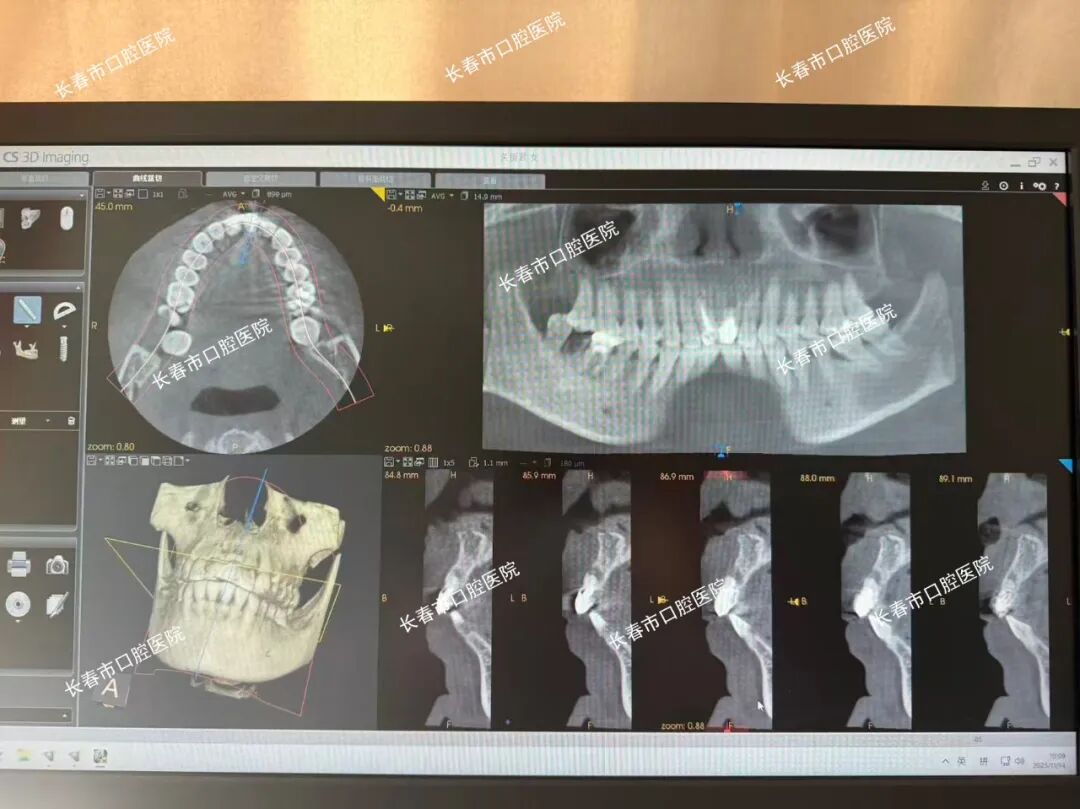

在手术过程中,王圣主任、李泽峰医生等医护团队首先通过口腔扫描和CBCT获取关女士的口腔数据,随后利用导航系统进行精准定位,在导航仪实时引导下,成功为关女士拔除左上1残冠和右下6、7残根,并植入种植体。